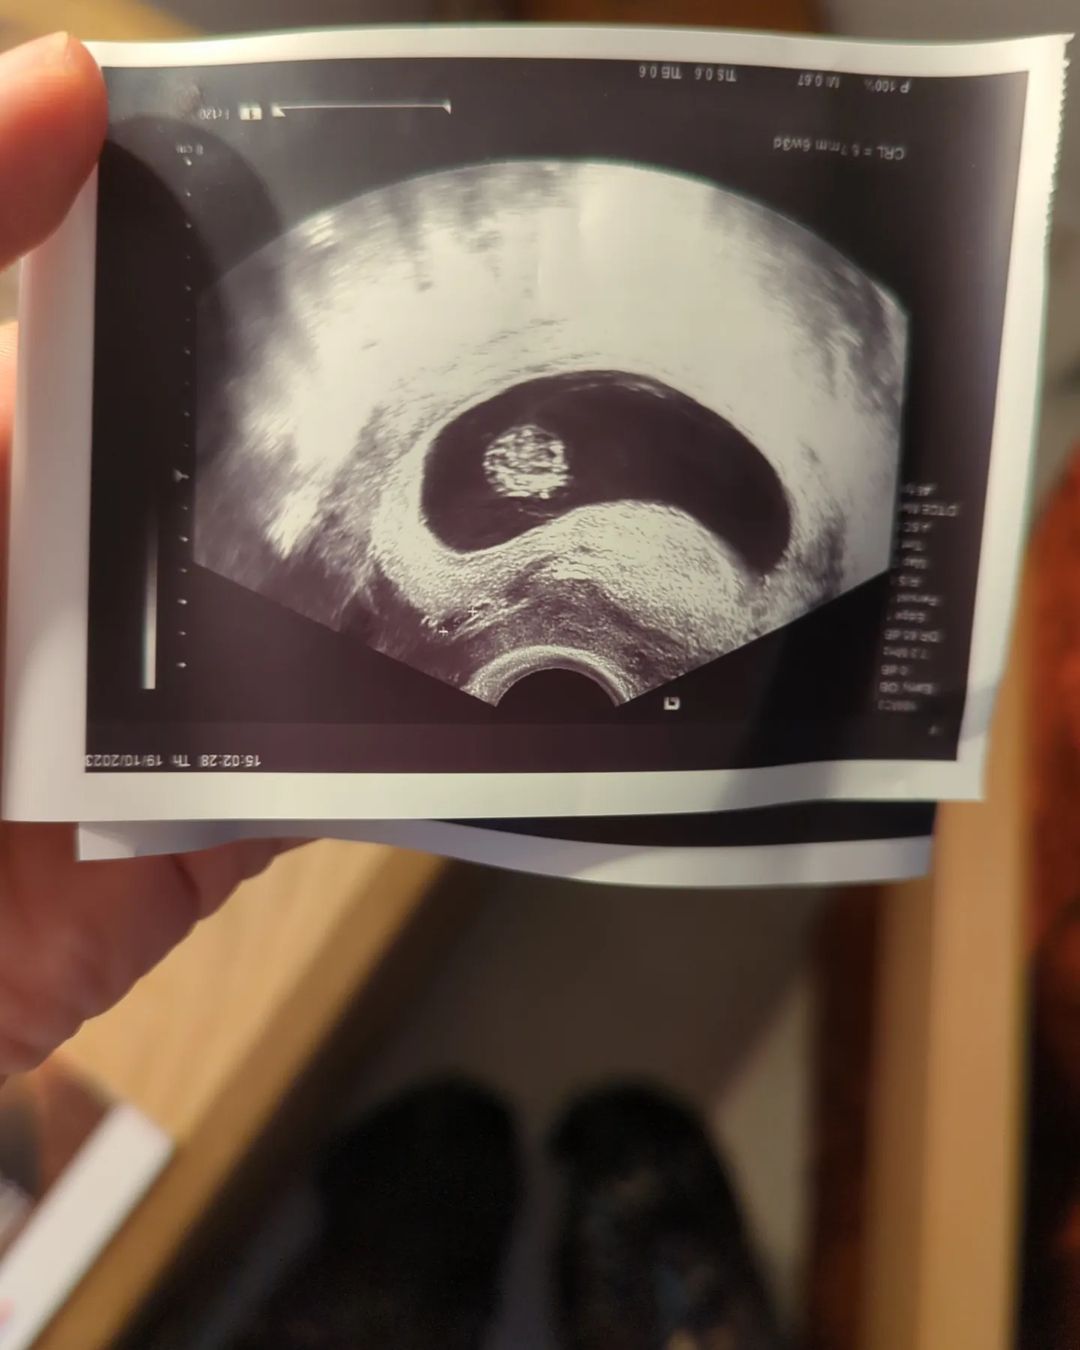

Η ίδια ανακοίνωσε τη χαρμόσυνη είδηση στο instagram δημοσιεύοντας μια σειρά φωτογραφιών από το τεστ εγκυμοσύνης μέχρι σήμερα. «Two souls, one body! So so so happy! #baby #ontheroad», έγραψε η ηθοποιός.